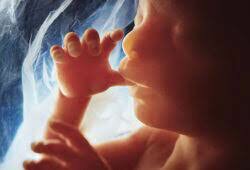

• Semana 17-19

Semana 17-19

También se está desarrollando el reflejo de succión, que le permite al bebé succionarse el pulgar. La piel de tu bebé se está haciendo más gruesa. En las niñas, se forman el útero y el canal vaginal.